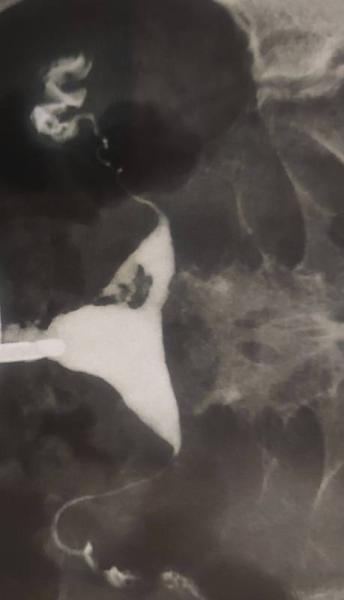

Hallo, ich hatte im Januar 2023 eine Ausschabung in 10SSW, im Juni hatte ich eine biochemische Schwangerschaft und im August hatte ich wieder eine Ausschabung in 7SSW. Nach der Ausschabung im August konnte ich fast 3Monate keine Periode bekommen. Dann habe ich hormonelle Pille genommen und endlich habe ich nach 4 Monate meine Periode bekommen. Vor 5 Tagen hatte ich HSG gemacht und meiner Frauenarzt meinte, dass ich Asherman syndrom habe. Er hat mir Hysteroskopie vorgeschlagen. Hat jemand so eine Erfahrung? Hatte jemand nach so eine OP erfolgreiche Schwangerschaft ? Gerne lade ich das Foto von HSG hoch.